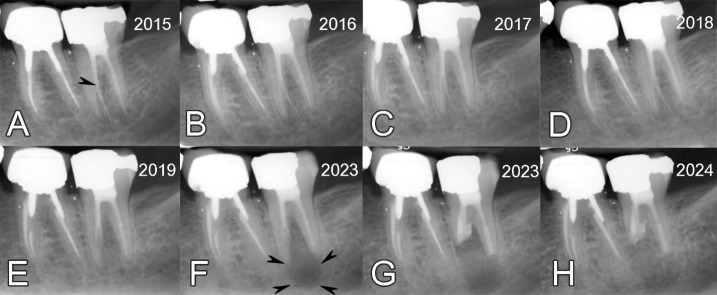

Strip perforation is a severe procedural complication during root canal therapy, often associated with poor prognosis, especially when combined with overextended gutta-percha. While surgical or nonsurgical retreatment is commonly indicated, patient-centered decision-making and long-term follow-up may influence the management strategy. This case report describes the conservative follow-up and eventual successful treatment of a mandibular second molar with an extensive midroot strip perforation and extruded gutta-percha, ultimately managed with intentional replantation and root-end filling using calcium-enriched mixture (CEM) cement. In 2015, a 40-year-old female patient presented for routine examination. A previously treated mandibular second molar (#37), which had a severe strip perforation in the mesial root and overextended gutta-percha one year prior, remained asymptomatic and functional. The patient declined retreatment and opted for annual monitoring. Over five years, the tooth remained functional and symptom-free, and the extruded gutta-percha showed gradual radiographic resorption. In 2023, the patient returned with a symptomatic apical periodontitis and a large periapical lesion associated with the same tooth. Intentional replantation was performed with midroot resection of the mesial root, root-end filling using CEM cement, and immediate replantation. At the 1-year follow-up, the tooth remained functional, asymptomatic, and radiographically healed. The case highlights the long-term clinical risks of untreated strip perforations, the unpredictable resorption of overextended materials, and the efficacy of minimally invasive surgical interventions in preserving tooth function.